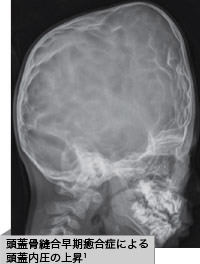

- 頭蓋骨縫合早期癒合症1

頭蓋骨縫合早期癒合症の合併症には次のような症状があります

- 頭蓋内圧上昇1,2